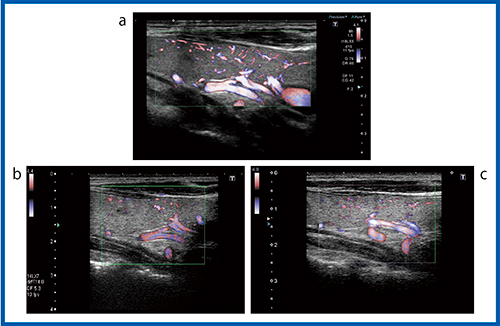

2)カラードプラ法

カラードプラ法の甲状腺の画像を供覧する。図4は正常な甲状腺のパワードプラ画像だが,Aplio XG(b)では深部の太い血管はよくわかるが,体表に近い部分は血流か,アーチファクトかの判断が難しい。Aplio 500(c)では体表に近い部分は血流であることはわかるものの,血管外へのはみ出し(ブルーミング)が強く血管像がぼやけて見える。Aplio i800(a)では,アーチファクトが減り細かい血流が明瞭に描出されている。充実性腫瘍の画像(図5)でも,全体の血流が描出されており,特にAplio i800(b)ではブルーミングが抑えられ細かい血流まで確認できる。また,カラードプラ法(CDI:図6)では,同様にAplio i800(b)の方が細かい血流まできれいに描出されている。

図4 超音波診断装置の進化:パワードプラ法(12MHz)

a:Aplio i800 b:Aplio XG c:Aplio 500

図5 パワードプラ法による充実性腫瘍の描出能の比較(12MHz)

a:Aplio 500 b:Aplio i800

図6 超音波診断装置の進化:カラードプラ法